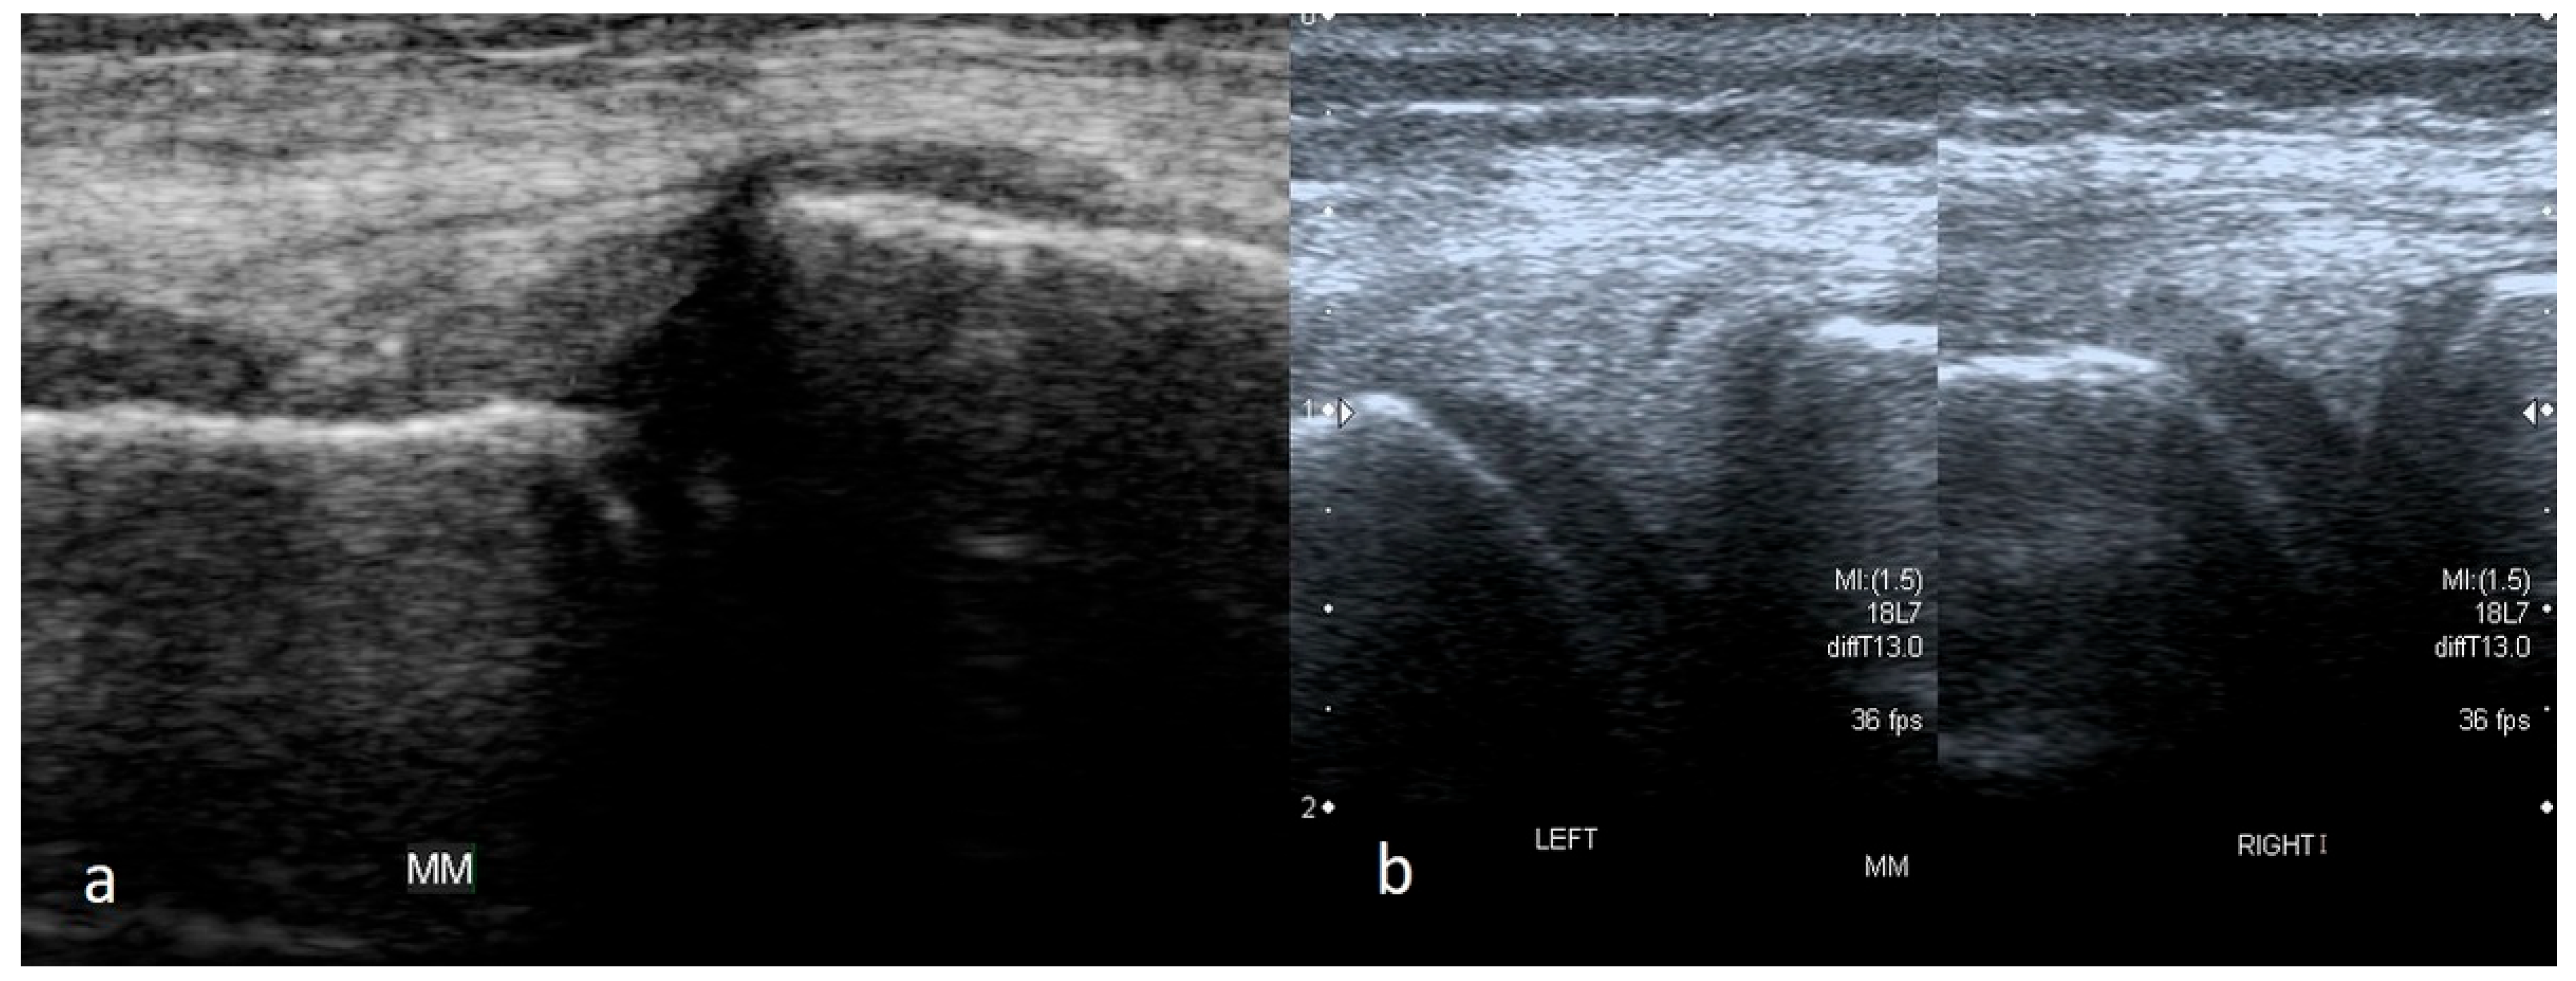

3.1.3. Bucket-Handle Tears

3.1.4. Meniscal Flap Tears